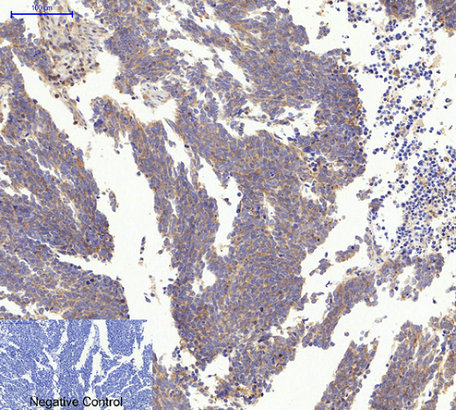

Immunohistochemical analysis of paraffin-embedded Human-stomach-cancer tissue. 1,Actin β Polyclonal Antibody was diluted at 1:200(4°C,overnight). 2, Sodium citrate pH 6.0 was used for antibody retrieval(>98°C,20min). 3,Secondary antibody was diluted at 1:200(room tempeRature, 30min). Negative control was used by secondary antibody only. |